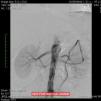

Around four months later, there was recurrence of exertional angina. At this time a difference in blood pressure between the arms was noted (20 mmHg less in the left arm), with a very weak pulse on the left and evident skin pallor immediately after exertion or when raising the left arm. Laboratory testing showed slight thrombocytosis and a rise in erythrocyte sedimentation rate to 100 mm/h. Echocardiography revealed new-onset hypokinesia of the left ventricular inferior wall, and coronary angiography was repeated, which showed preocclusive lesions of the right coronary artery and ostial saphenous graft. She underwent percutaneous coronary intervention with placement of two drug-eluting stents; during the procedure occlusion of the left subclavian artery was observed with retrograde filling from the ipsilateral vertebral artery (Figure 1), which raised the suspicion of Takayasu arteritis. Cranial computed tomography (CT) angiography confirmed proximal occlusion of the left subclavian artery upstream of the origin of the left vertebral artery (Figure 2), an atheromatous plaque in the distal segment of the right common carotid causing preocclusive stenosis of the external carotid, and tortuosity and kinking of the cervical course of the internal right carotid artery. Carotid Doppler ultrasound showed coiling of the right internal carotid and 70% stenosis, preocclusive stenosis of the right external carotid and reversal of flow in the left vertebral artery caused by left subclavian steal. Abdominal Doppler ultrasound detected no abnormalities in the renal arteries and the patient did not present nitrogen retention. In view of these findings and fulfillment of the diagnostic criteria, a diagnosis of Takayasu arteritis was made and therapy was begun with oral prednisolone 1 mg/kg/day.